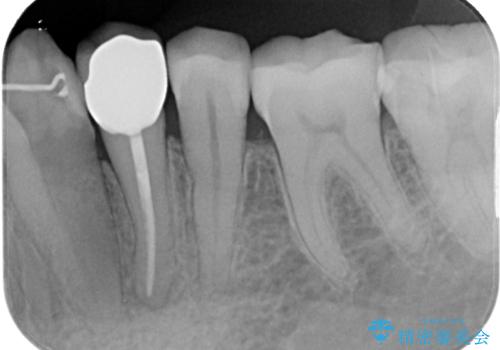

- 数日前から左下の奥歯がズキズキと脈をうつような痛みがあるとのことで来院された患者様です。

精査の結果、左下の第一小臼歯の虫歯が大きく進行していることが原因で痛みが出ていることがわかりました。

ラバーダム防湿を行ったうえで根管治療を行い、その後オールセラミッククラウンによる補綴治療を行っていくこととしました。

根管治療後すぐに痛みは消失しました。

根管治療後はクラウンによる補綴治療が必要です。